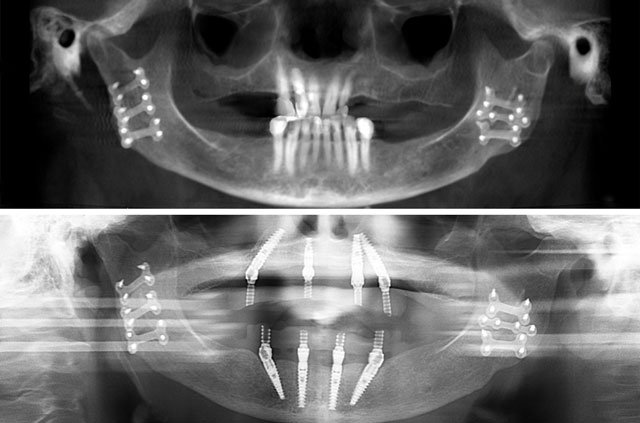

All-on-4 and immediate implant solutions for complete smile restoration. These cases showcase our expertise in full-arch rehabilitation with same-day teeth, providing patients with immediate functional and aesthetic results.

All-on-4 is a revolutionary dental implant technique that uses just four strategically placed implants to support a full arch of replacement teeth. The posterior implants are angled at 30-45 degrees to maximize bone contact and avoid anatomical structures like the maxillary sinus or inferior alveolar nerve. This innovative approach allows for immediate loading with a temporary prosthesis, providing same-day teeth and eliminating the need for lengthy healing periods between procedures.